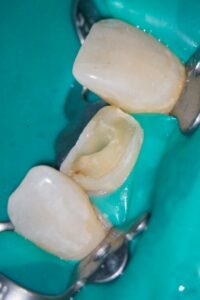

Das Zahnfragment hatte eine gute Passung auf den frakturierten Stumpf. So konnte im Vorfeld ein Silikonabdruck als Vorwall für den Kompositaufbau erstellt werden. Die endodontische Therapie sowie der Füllungsaufbau erfolgten ausschließlich unter dem hochauflösenden OP-Mikroskop (Zumax OMS2350). Die zu behandelnde Region wurde mit Ubistesin 1/200000 lokal betäubt. Anschließend wurde von 11 bis 22 ein Kofferdam angebracht. Der Zahn wurde mit einem konischen Diamanten trepaniert, die Trepanationsöffnung mit Gates-Glidden-Bohrern erweitert. Die Aufbereitung erfolgte mit dem Reciproc Blue System bis zur Größe 50.05.

Guttapercha und AH Plus als Sealer. Anschließend wurden aufgrund der ovalen Kavität zwei Glasfaserstifte zur Stabilisation der Füllung eingebracht und mit Luxacore adhäsiv verklebt.

Der provisorische Aufbau erfolgte durch den Endodontologen mit vorab gefertigtem Silikonschlüssel mittels Tetric Flow und Ceram A3,5 als Abschluss der Single-Visit-Behandlung. Die endgültige Krone konnte am 12. Juni 2025 eingegliedert werden.